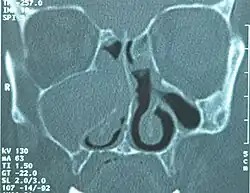

Eine Mukozele ist eine Ansammlung (-zele) von Schleim (lateinisch mucus) in einem Hohlraum (meist Nasennebenhöhlen) auf Grund einer Abflussbehinderung des Schleimes durch Verschluss des Ausführungsganges.

Bei Mukozelen der Nasennebenhöhlen ist die Folge ein Abbau der knöchernen Wände mit Vorwölbung der Mukozele im Bereich der Nase und der Augenhöhle.[1] Große Mukozelen der Stirnhöhle und des Siebbeins können zu einem Exophthalmus führen, den Augapfel bedrängen und seine Beweglichkeit einschränken.